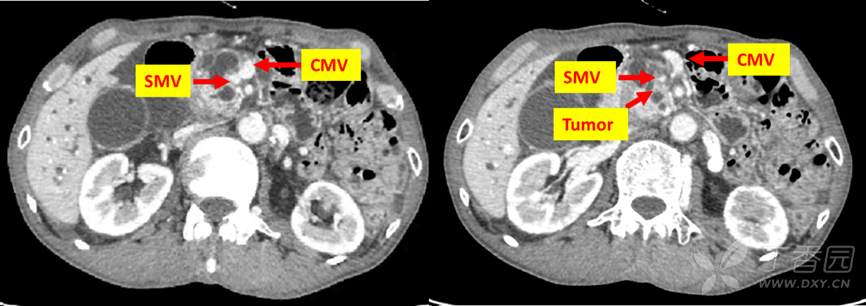

69岁男性,因纳差乏力3月,皮肤巩膜黄染2月,检查发现胰腺勾突癌入院。既往史3年前行双髋关节置换术,余无特殊。化验总胆红素121.6μmol/L,CA199:101.5U/mL。影像检查如下:

动脉系统评估,腹腔干及SMA未收侵犯,结肠中动脉可疑受侵犯。

肠系膜上静脉系统评估,结肠中静脉以下部分被肿瘤侵犯。